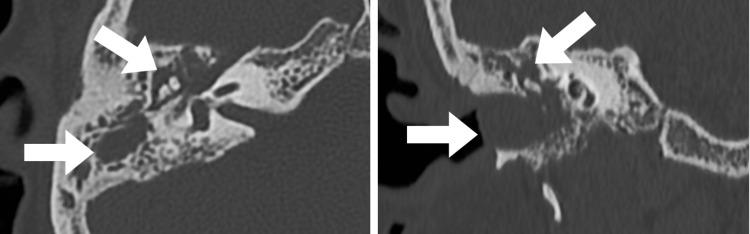

Head and neck paragangliomas are rare neuroendocrine tumors arising from the autonomic nervous system. Imaging hallmarks of paragangliomas of the head and neck include an enhancing soft-tissue mass in the carotid space, jugular foramen, or tympanic cavity on computed tomography; a salt-and-pepper appearance on standard spin-echo magnetic resonance imaging; and an intense blush on angiography. Imaging studies depict the location and extent of tumor involvement, help determine the surgical approach, and predict operative morbidity and mortality. However, an atypical presentation of paragangliomas, especially when co-existing with other middle ear pathologies that have overlapping imaging findings, can often be misleading. Here, we report a case of simultaneous occurrence of paraganglioma, cholesteatoma, and otomastoiditis in a young adult female.